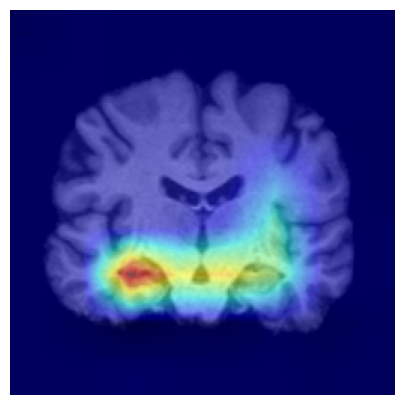

Results.

Figure 7 indicates the qualitative results. Our explainability method consistently highlights the hippocampal and medial temporal lobe regions, and the resulting heatmaps show strong correspondence with areas affected by hippocampal atrophy. These results supports that the identified regions align with established AD biomarkers.